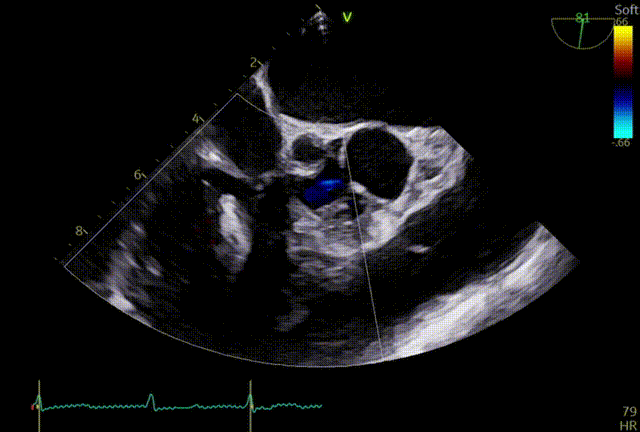

术后TTE:夹合器稳定,三尖瓣轻度反流

患者全麻后,在经食道超声心动图和DSA引导下经股静脉穿刺,送入导丝建立右心房通路,沿导丝将22F可调弯导引鞘组送入右房,再沿导引鞘管送入一枚夹合器至右房,在超声食道中段RV Inflow/Outflow切面和经胃三尖瓣短轴切面多次切换引导下,调整夹合器夹合位置,使夹合器顺利到达三尖瓣前叶与隔叶间反流最大区域,跨瓣后进行瓣叶捕获和夹合,后经食道超声心动图确认瓣叶夹层牢固及有效长度,释放夹合器。患者术后即刻超声心动图评估三尖瓣反流1+,肝静脉逆流较前明显减少。